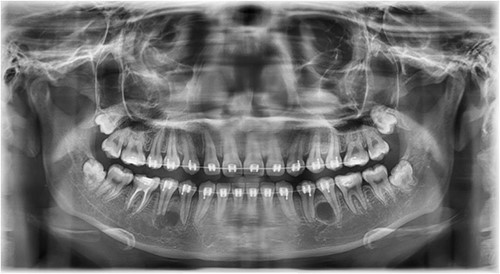

A 21-year-old patient with a non-contributory history reported to the clinic with a complaint of spacing in the anterior teeth. On radiographic examination, eumorphic supernumerary premolar crowns were found located between the roots of the mandibular first and second premolars (Fig. 1). The patient was completely asymptomatic and had no knowledge regarding the presence of these accessory teeth.

Image depicting the supernumerary premolar buds located between the first and second mandibular premolars.